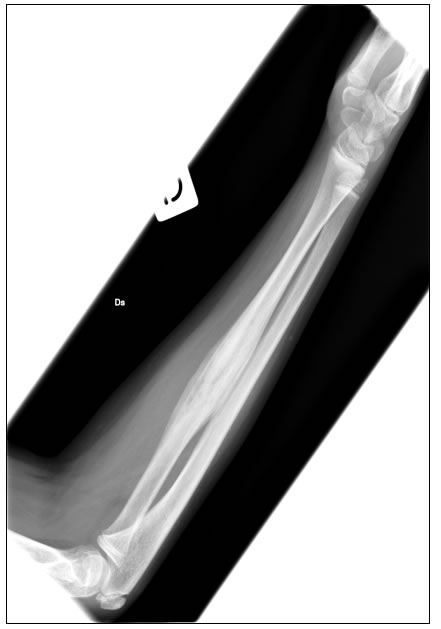

Il successivo decorso clinico si caratterizza per la comparsa di dolori agli arti superiori, con evi-denza di lesioni radiografiche di osteite-iperostosi disreattiva multifocale (figura 5).

A fronte di questa ripresa della malattia la diagnosi diventa naturalmente più semplice, ed è quella di una Osteomielite Multifocale Cronica Ricorrente (CRMO); viene avviata terapia steroidea, con successivo programma di lento scalo e prosecuzione con FANS.

Figura 5: il radiogramma dell'avambraccio mostra una zona di alterazione della struttura ossea a livello del ra- dio, in gran parte osteoaddensante, con piccole aree di rarefazione nel contesto.